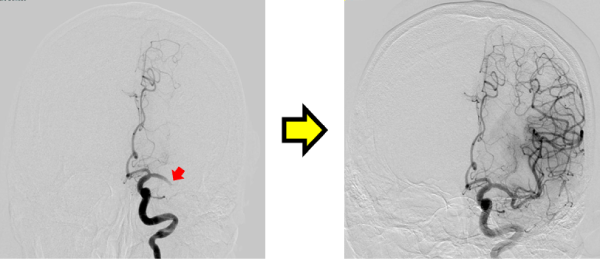

3. 脳血管内治療

脳梗塞の原因となる頸動脈狭窄症や、くも膜下出血の原因である脳動脈瘤に対しては、従来の脳神経外科的な手術(頸動脈内膜剥離術、脳動脈瘤クリッピング術)が行われてきましたが、より低侵襲で安全性や有効性が示されている脳血管内治療(頸動脈ステント留置術、脳動脈瘤コイル塞栓術)も可能になっています。

当院でも、脳血管内治療を積極的に行っておりますが、治療方針については、脳神経外科と連携し、患者さんとご家族にとって最適な治療が選択できるよう努めています。

その他、頭蓋内外の動脈の血管形成術や頭頸部の腫瘍に対する塞栓術など、幅広い脳血管内治療を行っています。